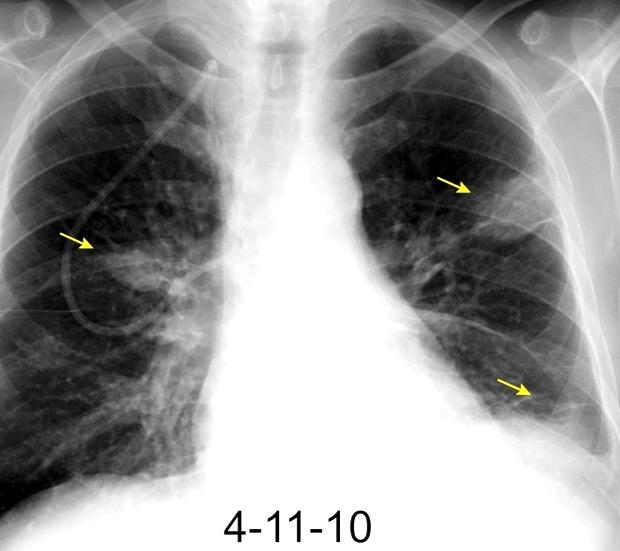

NEUMONITIS POR RADIACIÓN

Neumonitis evidente de 4-12 semanas después de terminar RXT. Fibrosis evidente en 3-4 meses. Estable de 912 meses.

Ca. de mama izquierda. 3/7/09 Radioterapia

La lesión típicamente limitada al campo de irradiación.

Müller NL. 2010

Induce neumonitis. “Tangential beam” para pared torácica.

Jung JI et al. Thoracic Manifestations of Breast Cancer and Its Therapy. Radiographics 2004